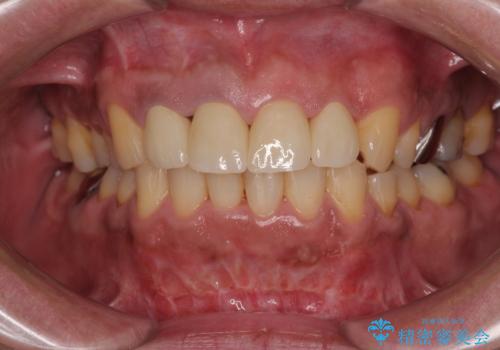

骨格性のディープバイト 補助装置を併用したワイヤー矯正治療で咬み合わせを改善